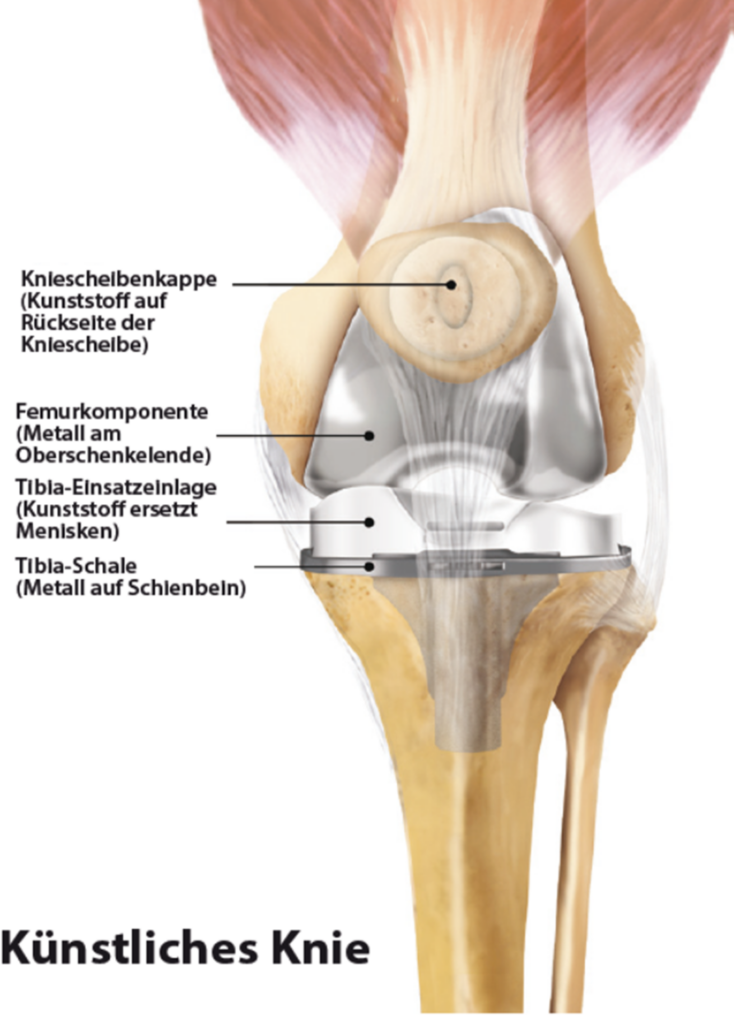

Bei der Kniegelenksarthrose wird die verschlissene Knorpeloberfläche der Gelenkpartner durch eine Metalloberfläche ersetzt („Oberflächenersatz“). Als Gleitschicht zwischen beiden Komponenten dient ein sog. Inlay aus Polyethylen.

Ist nur die Innenseite des Kniegelenks verschlissen, kann eine sog. Unicondyläre Endoprothese („Schlittenprothese“) eingesetzt werden.